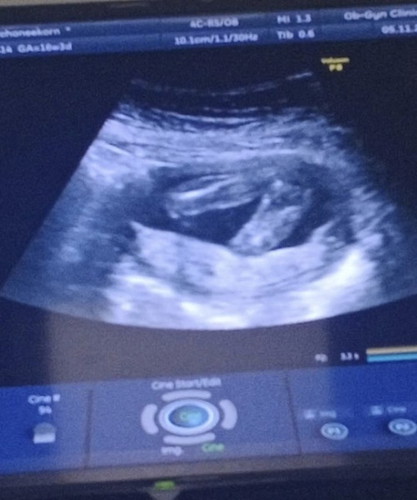

รบกวนสอบถาม แบบนี้มีโอกาสเป็นผู้ชายมั้ยคะ 😄

อายุครรภ์ 4เดือนพึ่งไปซาวด์วันนี้ หมอบอกน่าจะผู้หญิง แต่ในใจหวังลึกๆ อยากให้เป็นผู้ชาย

ผู้หญิงจ้า หมอบอกไม่มีอะไรโด่เลย สมใจพ่อเขาเลย😁

คำว่าน่าจะของหมอคือยังไม่ฟันธง100%คะ โอกาศมีเสมอ